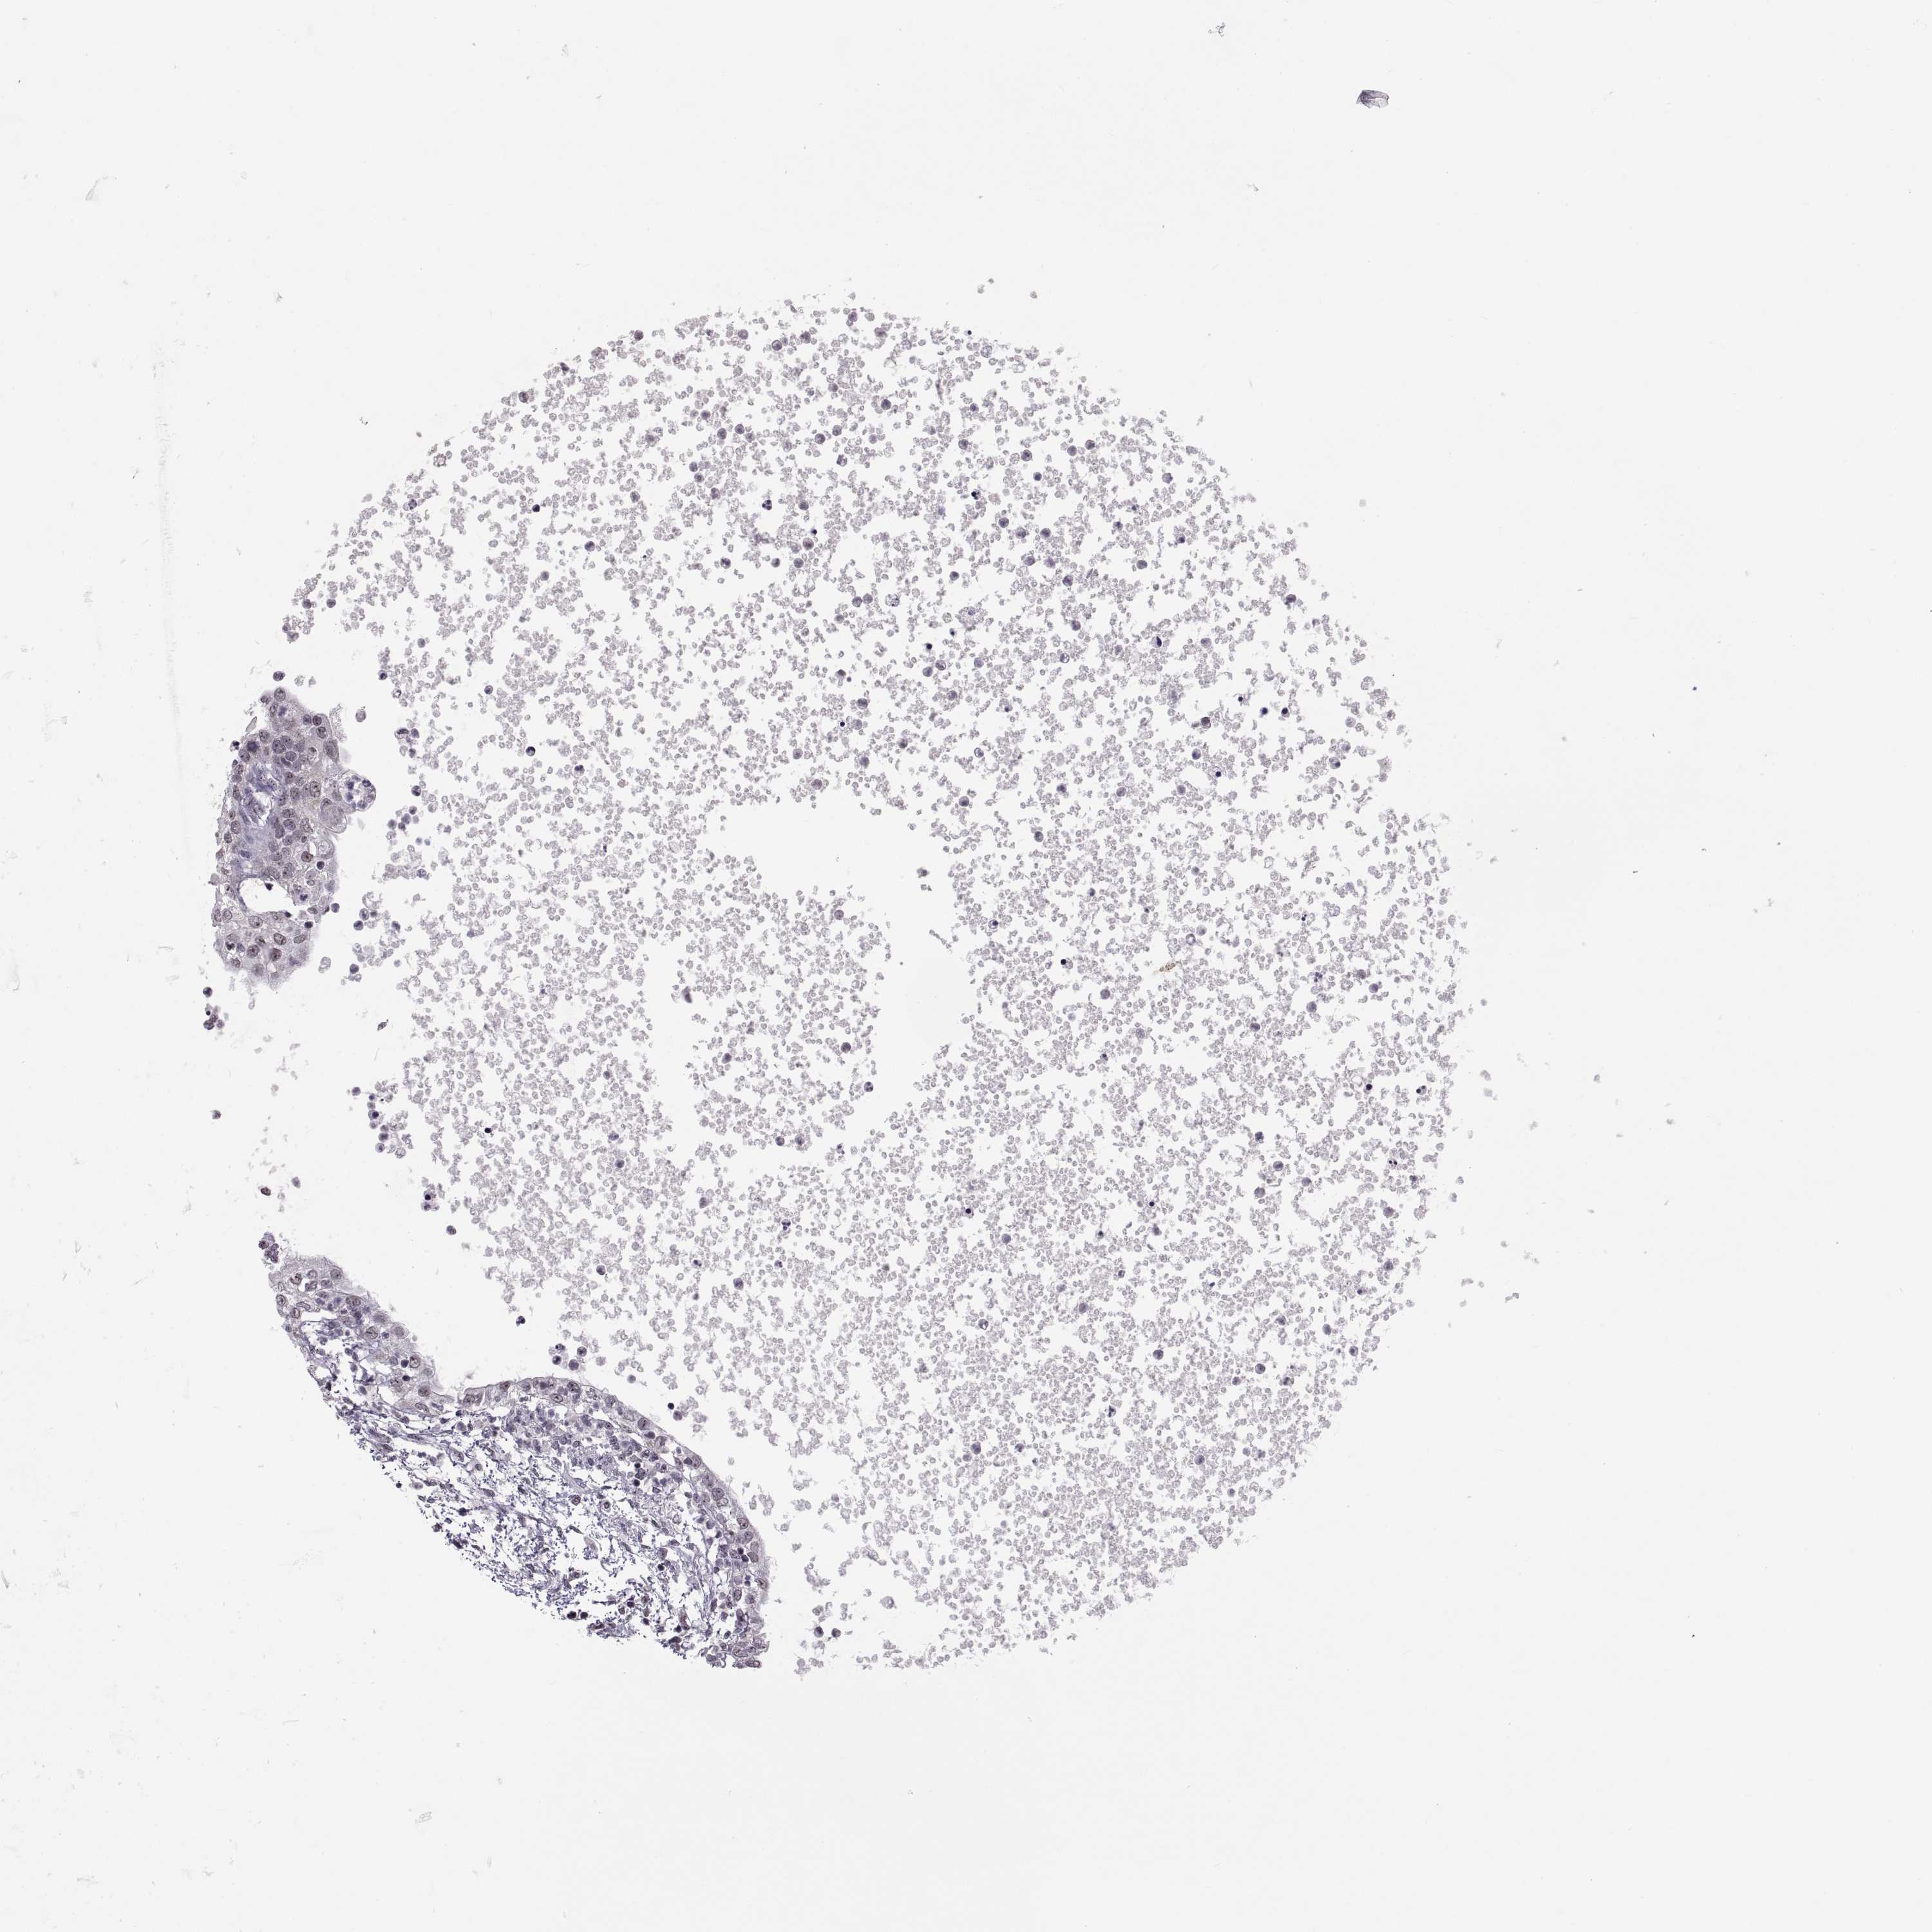

TESTIS CANCER - Protein expressioni

A mouse-over function shows sample information and annotation data. Click on an image to view it in a full screen mode. Samples can be filtered based on level of antibody staining by selecting one or several of the following categories: high, medium, low and not detected. The assay and annotation is described here.

Note that samples used for immunohistochemistry by the Human Protein Atlas do not correspond to samples in the TCGA dataset.

Antibody stainingi

Antibody staining in the annotated cell types in the current human tissue is reported as not detected, low, medium, or high, based on conventional immunohistochemistry profiling in selected tissues. This score is based on the combination of the staining intensity and fraction of stained cells.

Each image is clickable and will lead to virtual microscopy that enables deeper exploration of all samples and also displays staining intensity scores, fraction scores and subcellular localization as well as patient and tissue information for each sample.

Antibody HPA059342

Seminoma, NOS

Carcinoma, Embryonal, NOS

Teratoma, malignant, NOS